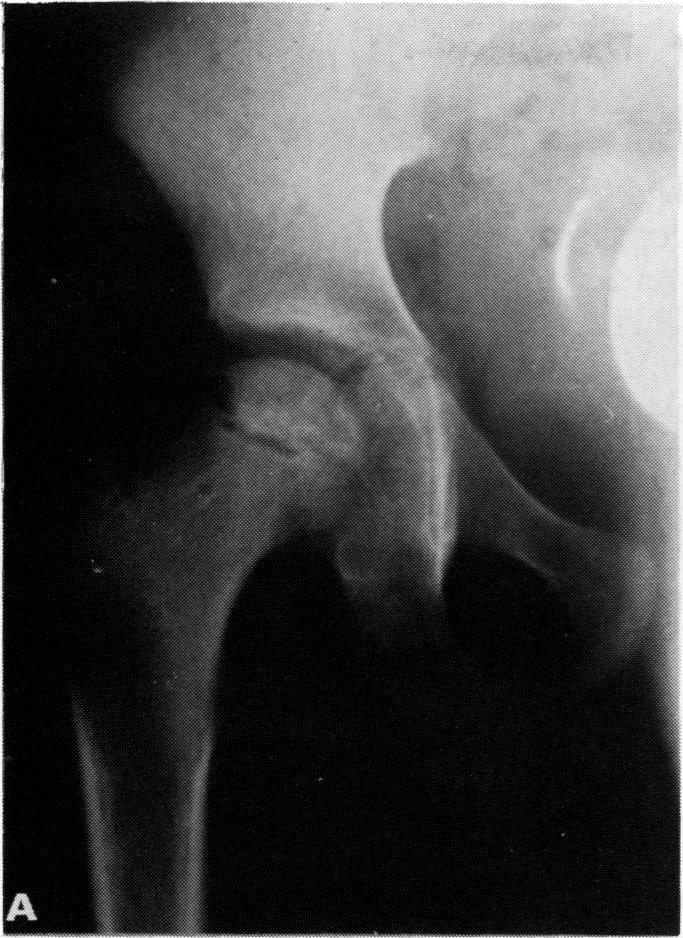

The case is reported of a 7 year old Bedouin girl who presented with a three week history of fever and limp. Initial tests for rheumatoid factor, antinuclear antibodies, and brucella were negative. Two weeks after admission Brucella melitensis was cultured from bone marrow and synovial fluid samples. The patient improved after treatment with doxycillin and streptomycin, but radiographs of the right hip showed avascular necrosis of the right femoral head. A mild limp and limitation of motion in the right hip persisted 18 months after admission.

报告了一例7岁贝都因女孩的病例,她有三周的发热和跛行病史。类风湿因子、抗核抗体和布鲁氏菌的初步检测均为阴性。入院两周后,从骨髓和滑液样本中培养出羊种布鲁氏菌。患者在接受强力霉素和链霉素治疗后病情好转,但右髋部X光片显示右股骨头缺血性坏死。入院18个月后,右髋部仍有轻度跛行和活动受限。